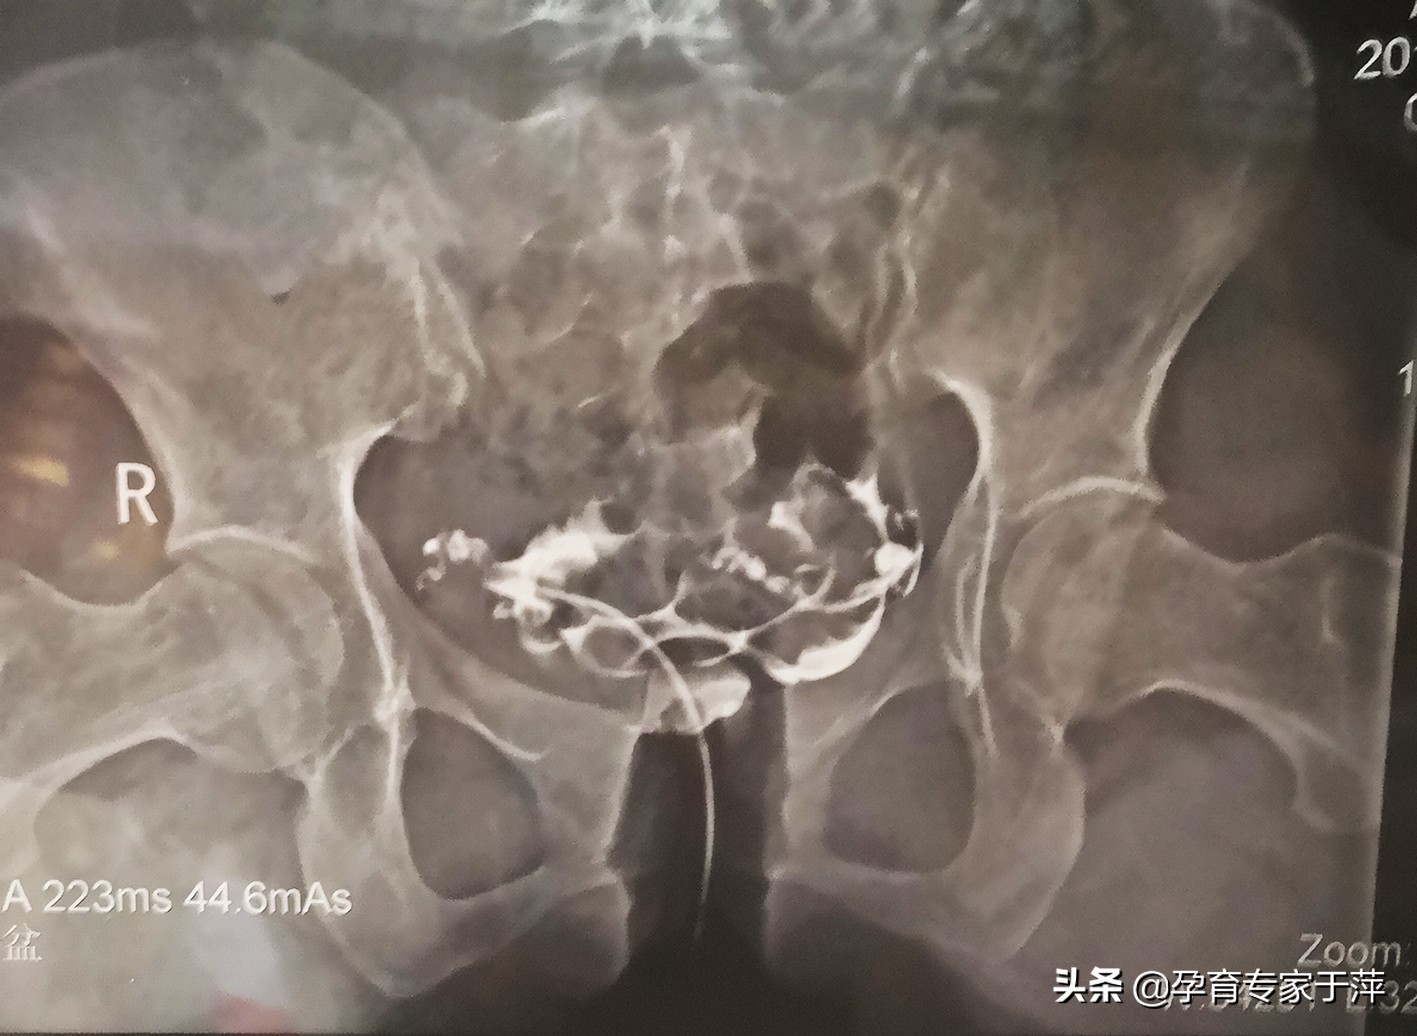

患者比较高,大约有1.75米,比较瘦,体重只有105斤。由于患者存在长期月经不调,给患者查了激素6项,同时给患者检查了人抗苗勒试管激素(AMH)看看卵巢功能怎么样,考虑到患者结婚两年了,建议患者做了输卵管造影,看看输卵管有没有问题。经过检查,最终确诊为:原发不孕,月经不调,子宫右偏,输卵管右侧粘连成团通而不畅,左侧通而不畅;卵巢功能减退、甲状腺功能低下。